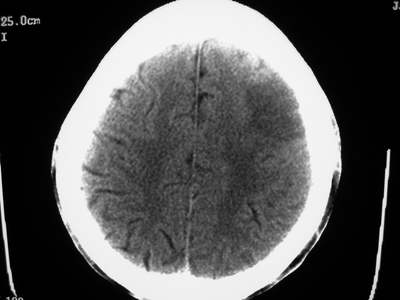

以下是引用卜一在2007-1-19 15:29:00的发言:[br]治疗前:1月14日右侧额叶皮质下低密度影,而治疗后:1月18日右侧阴影消失,新近出现左侧额叶侧脑室前角旁大片状低密度影,边缘模糊。支持—双侧额叶后部缺血性脑梗塞。